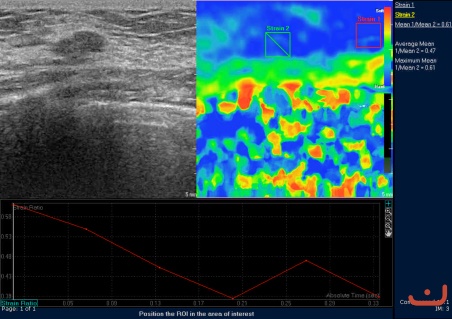

Case 57-E1

Benign solid mass

Friday, 22 May 2015